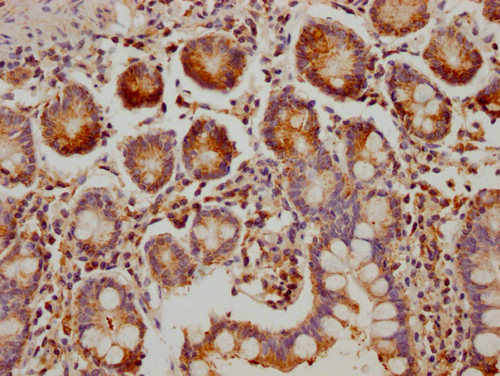

IHC image of CSB-PA875718LA01HU diluted at 1:300 and staining in paraffin-embedded human small intestine tissue performed on a Leica BondTM system. After dewaxing and hydration, antigen retrieval was mediated by high pressure in a citrate buffer (pH 6.0). Section was blocked with 10% normal goat serum 30min at RT. Then primary antibody (1% BSA) was incubated at 4°C overnight. The primary is detected by a Goat anti-rabbit polymer IgG labeled by HRP and visualized using 0.05% DAB.